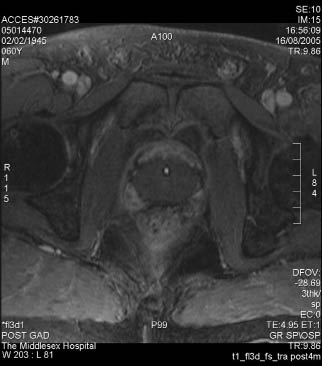

In 1995, a study at Indianapolis University showed that the whole prostate could be treated without damaging the prostate capsule or the rectal wall. In 1999, Dr. Toyaki Uchida, in Japan, began treating patients using the first commercially available Sonablate HIFU device, the Sonablate 200. In 2001, the Sonablate 500 was approved for use in Europe. Figure 1 shows the Sonablate 500 device. At the end of 2005, Health Canada approved the use of the Sonablate 500 for the treatment of prostate cancer. On March 12, 2006, I performed the first HIFU procedure using this device on a Canadian patient, in Toronto. Since then, over 500 men with prostate cancer have been treated in Toronto with HIFU performed using the most recent model, the Sonablate 500 version 4. Use of the Sonablate has not yet been approved by the US Food and Drug Administration (FDA) for the primary treatment of prostate cancer. However, an FDA-approved trial for men who have failed primary external beam radiation treatment for prostate cancer is currently being conducted in the United States and Canada. The case report in Figure 2 describes a patient in this study.

9) Retained “slough” that is preventing adequate bladder emptying can usually be resected or scraped out with a cold loop. The ultimate goal is that, after the sloughing of the ablated tissue, there will be a significant prostate defect as shown in the MRI images before and after HIFU treatment, Figure 5.